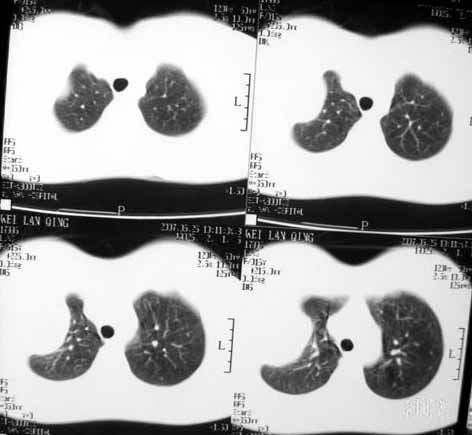

[br]病灶定位在肋骨上,原因如图[br]定性支持邓老师的动脉瘤样骨囊肿、骨纤[br]巨细胞瘤较少发生钙化,所以我不考虑[br]桨细胞瘤不会发生膨胀性改变吧,经验少期待老师们的指正[br]骨结核内大多有沙粒状钙化,所以可能性也不大